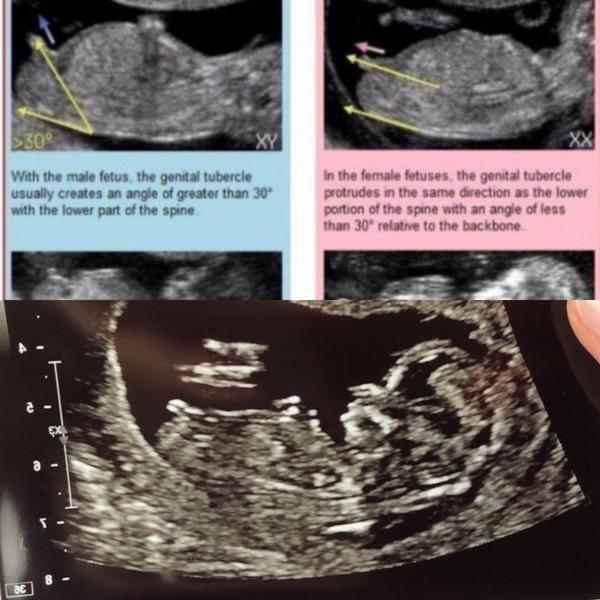

@petaov právěže se to dá poznat 🙂

takhle to poznala i doktorka, pak mrkla zespodu mezi nožky a ještě si to jakoby potvrdila, ale v 1.trimestru se to poznává právě podle fotky z profilu 🙂

@martina_cz díky, přesně tuhle fotku sem sem chtěla dát, to jen k tématu, že se pohlaví nedá poznat z profilu. Vid, že je to jasná pipka :D ♥